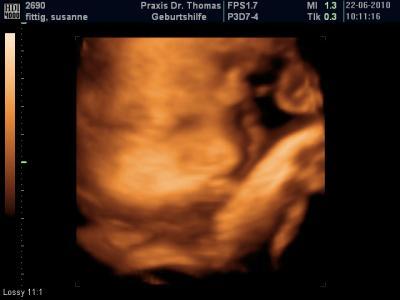

so heute wieder Vu ein Paar kleine Wehen sind drauf gewesen , sonst soweit alles ok Gewicht hab ich jetzt +9 kg Muttermund ist weich und fingerkuppendurchlässig was immer das auch heißen mag nächster Termin ist am 6.7. und er hat noch mal auf den Kleinen geschaut und ne süßes 3D bildchen gemacht

Bild zu vu in der 36+4 - Forum für Juli - Mamis